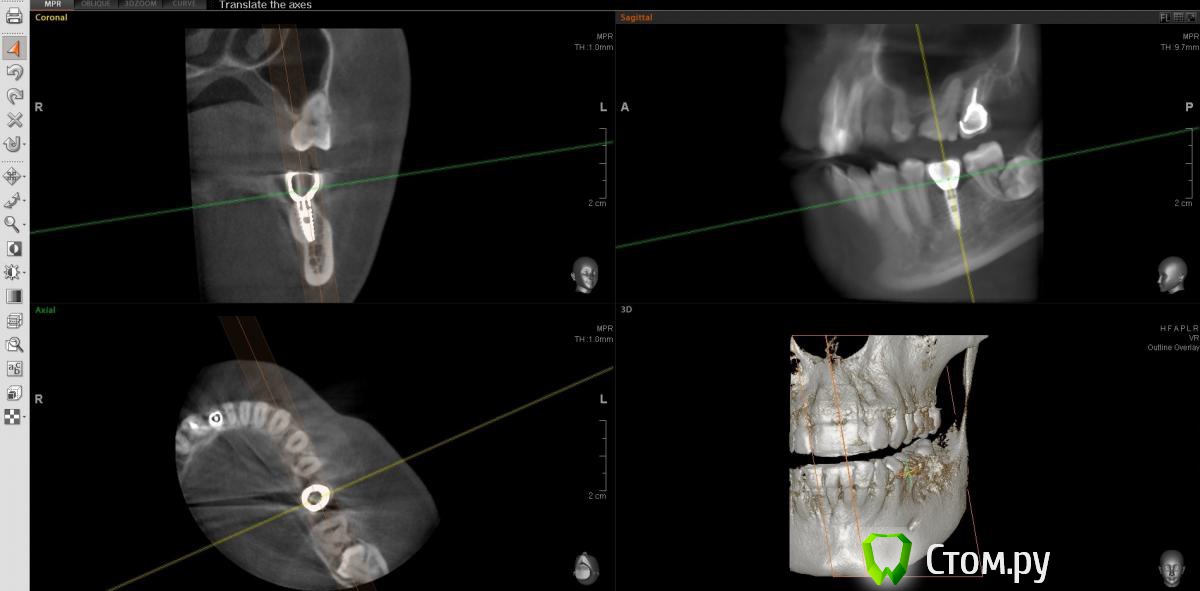

englishlady Опубликовано 6 мая, 2014 Автор Поделиться Опубликовано 6 мая, 2014 http://s019.radikal.ru/i620/1405/43/6a807f37e98f.png[/url] Ссылка на комментарий

englishlady Опубликовано 6 мая, 2014 Автор Поделиться Опубликовано 6 мая, 2014 Еще один срез. Если надо сделать как-то по-другому, постараюсь сделать. Просто последний стоматолог, у которого была, говорил о дополнительном канале.http://i031.radikal.ru/1405/cd/b5f5dd83e07f.png[/url] Ссылка на комментарий

englishlady Опубликовано 9 мая, 2014 Автор Поделиться Опубликовано 9 мая, 2014 Еще КТ. Может можно что-нибудь сказать про дополнительный канал и наличие воспаления.http://i023.radikal.ru/1405/76/586c872dc148.png[/url] Ссылка на комментарий

englishlady Опубликовано 9 мая, 2014 Автор Поделиться Опубликовано 9 мая, 2014 Еще КТ.http://i049.radikal.ru/1405/53/b0585c1cf7cd.png[/url] Ссылка на комментарий